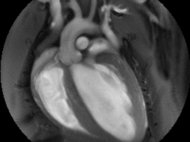

Imaging Platform

The central imaging core facility at the MPI for heart and lung research, provides a wide range of services and trainings, project specific support and full services for more than 100 scientists at the institute as well as for their collaboration partners. We also offer training for image analysis, develop custom analysis pipelines and help with data storage and archiving.